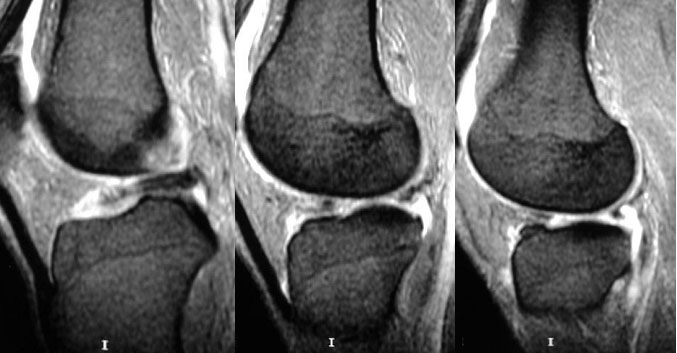

SIGNO DE LA PAJARITA AUSENTE

En los cortes sagitales de resonancia magnética de la rodilla, el cuerpo del menisco normal se parece a una pajarita (o corbata de lazo), es decir, se ven dos triángulos que apuntan uno al otro y se unen en el centro. Con cortes de 5 mm, debe verse en dos cortes consecutivos.

El signo de la pajarita ausente consiste en que el cuerpo del menisco es visible en menos de dos cortes consecutivos. Esto indica que existe una rotura longitudinal del cuerpo meniscal con desplazamiento del fragmento interno (rotura «en asa de cubo»).

Arriba a la izquierda: plano axial que muestra los meniscos normales. Arriba a la derecha: esquema de una rotura en “asa de cubo” del menisco externo. Las líneas rojas representan los planos de corte coronal.

Abajo a la izquierda: esquema del corte coronal en el menisco normal en el que se ve la imagen de pajarita. Abajo a la derecha: el signo de la pajarita ausente en la rotura meniscal.